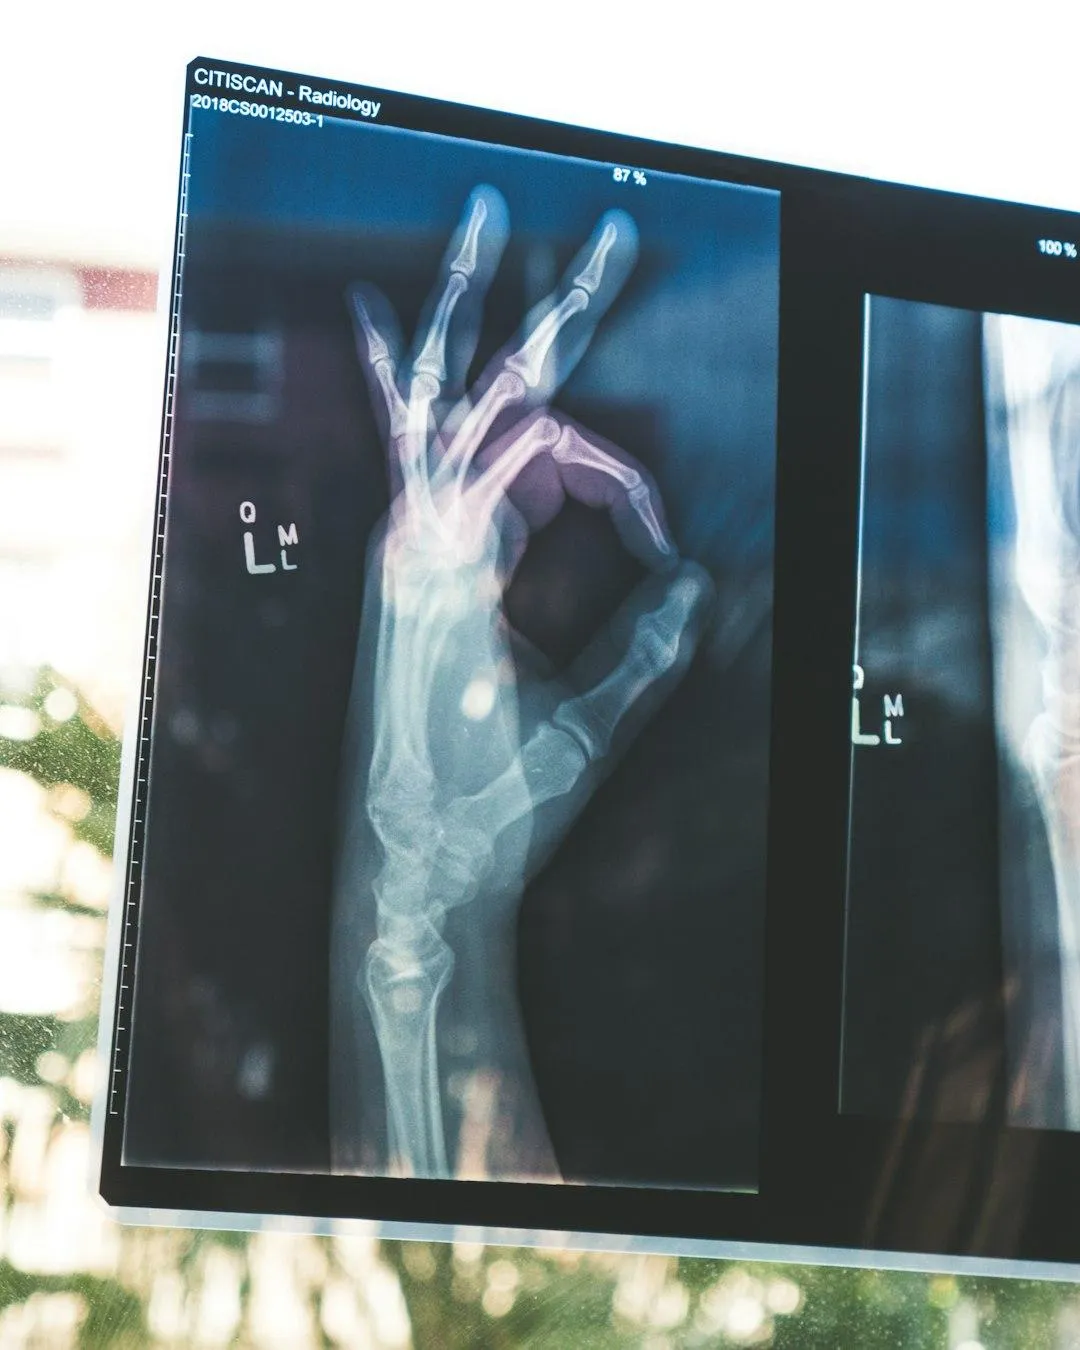

Master Fracture Detection: Learn how to quickly identify common and complex fractures with precision.

Increase Diagnostic Confidence: Develop a sharper eye for fractures with targeted techniques that help you make accurate decisions quickly, reducing errors and enhancing your clinical performance.

Download "Boost Your Fracture Detection Skills by 80% in Just 5 Minutes" to improve diagnostic accuracy and confidently identify fractures.